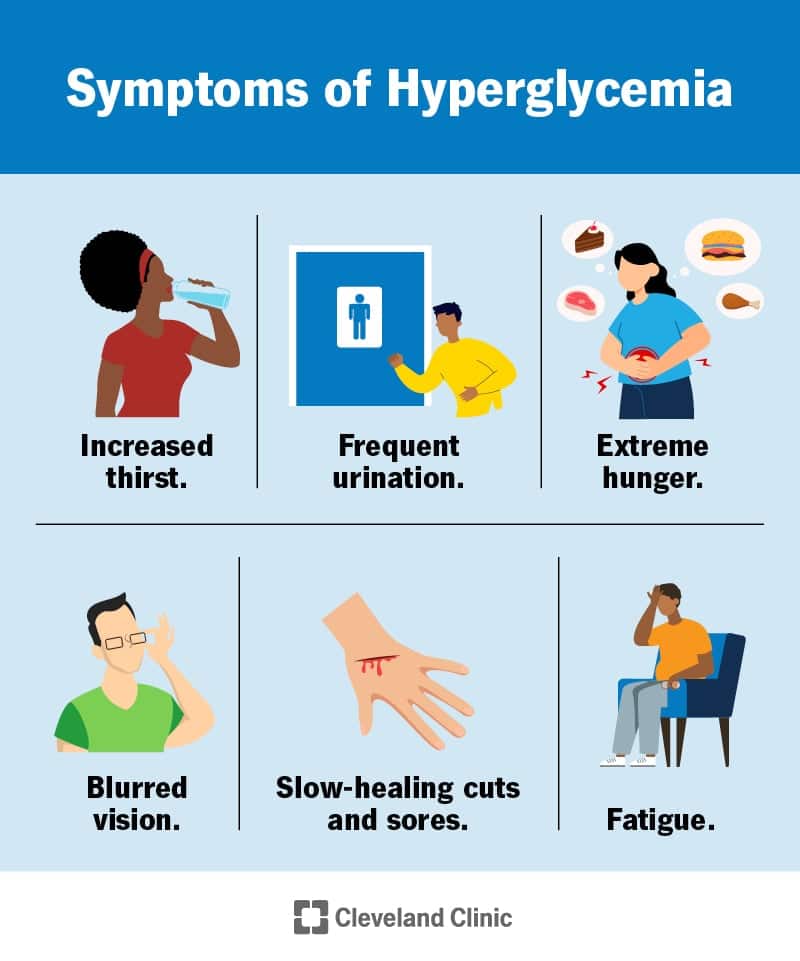

H pergl keemia k rge Veresuhkur S mptomid Ja Ravi SFOMC

High Blood Sugar You Don t Need To Worry About Keto Carnivores Relax